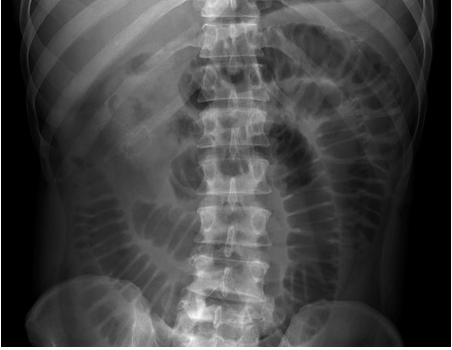

Q

What does this show?

Sigmoid volvulis - coffee bean sign

• sigmoid is very dilated due to twisting at the root of the mesentery in the left iliac fossa

• proximal bowel also dilated

• dilated loop points upwards towards diaphragm

• high risk of perforation